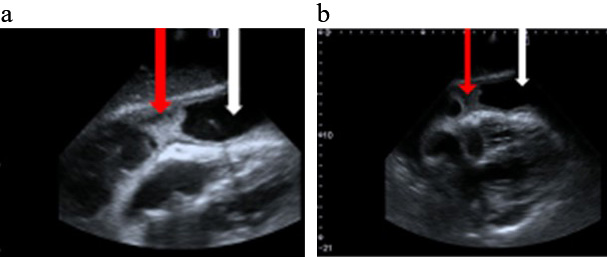

In the initial phase of PP the diagnosis may be facilitated by an echocardiographic image suggesting a purulent aetiology of the pericardial fluid: a dense fluid character with the presence of an epicardial fibre layer or the formation of a fluid space separated by fibrin deposits (Figs. 1,2).

Fig. 1.

Fig. 1.Bedside echocardiography (a,b) Modified sub-sternal views. White arrow a large amount of fluid in the pericardium. Red arrow fibrin deposits in the pericardium space.

Fig. 2.

Fig. 2.Bedside echocardiography. A modified apical view. White arrow a large amount of fluid in the pericardium. Red arrow fibrin deposits in the pericardium space.